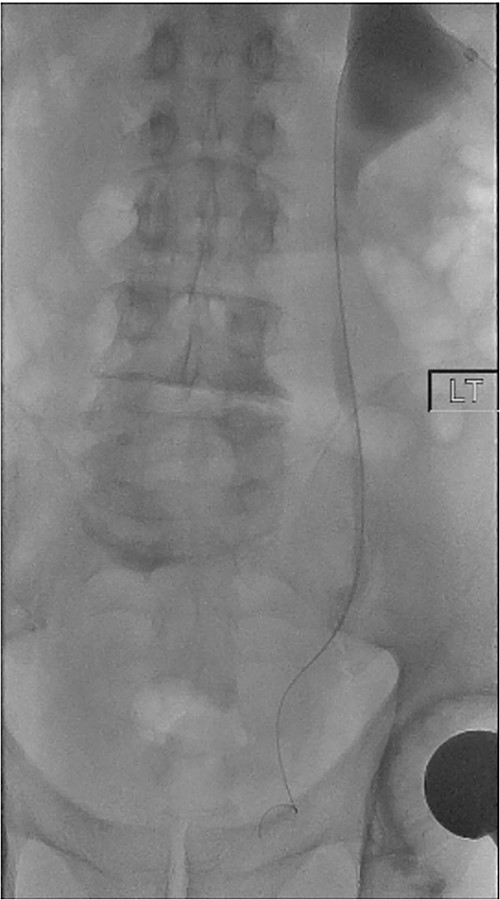

On Day 5 post-operatively, bilateral nephrostograms revealed bilateral ureteric occlusion at the level of the VUJ with extravasation at the right side (Fig. 1). An attempted antegrade ureteric stent insertion failed. The patient was thereafter booked electively for a rigid cystoscopy and bilateral ureteric stenting 3 weeks following the original operation.